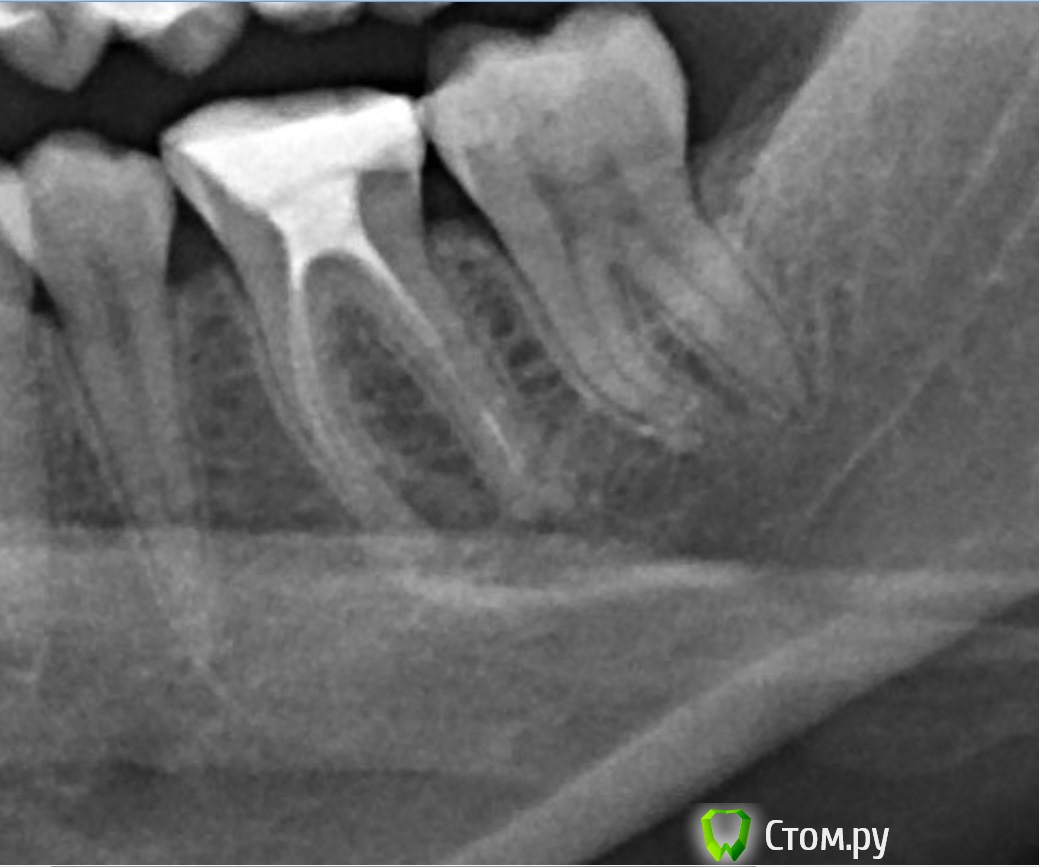

felicidade Опубликовано 23 июня, 2014 Автор Поделиться Опубликовано 23 июня, 2014 ИванК, спасибо за ответ! Затеплилась надежда Откопала ещё два снимка, где частично виден зуб №36 (первый снимок уж больно плохого качества, эти получше, хоть и не целиком показывают зуб). Ссылка на комментарий

DokDent Опубликовано 23 июня, 2014 Поделиться Опубликовано 23 июня, 2014 Вот ещё один снимок с Вашей панорамки. Теоретически можно перелечить и восстановить, но это 2-мерное изображение, поэтому по нему трудно судить об истинной картине что с корнями и вокруг них. Всё же лучше перед вмешательством посмотреть на кт. 1 Ссылка на комментарий